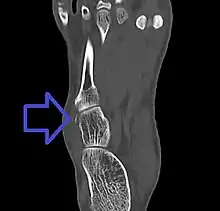

| Avulsion fracture of the right cuboid bone of the foot | |

Avulsion fracture of the cuboid on CT